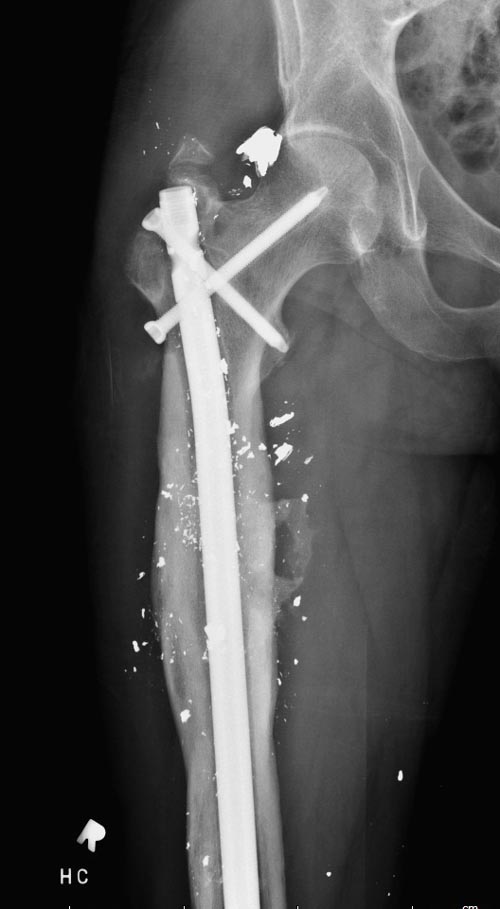

На снимках осложнение огнестрельного перелома бедра поздней инфекцией. 7

лет назад оперирован: правое бедро, сперва на ExFix, затем заменен на

гвоздь, а левая - гвоздь при поступлении.

Беспокойство проявил недавно, по поводу жалоб на боли сделано МРТ и

дренирование абсцесса терапевтами. Мы удалили гвоздь, сделали I&D,

рассверливание канала, и ввели гвоздь с антибиотиком. Для гвоздя

использовали стерильную трубку-форму, а антибиотик по 1.0 Tobramycin c

Vancomycin.